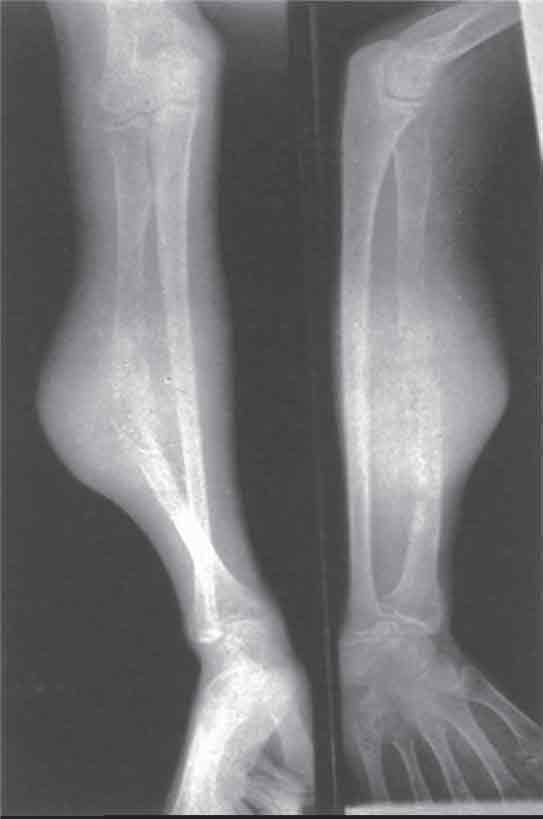

|

إوينغ: كسر مرضي بالكعبرة. |

| |

ساركومة إوينغ في عظم الظنبوب، بنت في سنّ 14 سنة (علامة قشر البصل). | صبي في سنّ عشر سنوات: إوينغ شديد الخبث في العضد. |